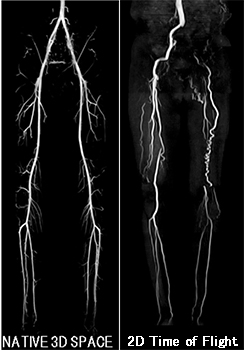

[下肢アンギオ撮像症例]

このVer.23による特徴は、動きや呼吸に伴うアーチファクトの制御です。かつてない高精細なイメージングで、幅広い検査部位への対応、3D Delta Flow 非造影MRAパッケージによる血管撮影時のタイミングのズレの排除、スキャン時間の低減等、新しい脂肪抑制法 “IDEAL-FLEX”など最新アプリケーションを装備しています。

“3D Delta Flow 非造影MRAパッケージ”

Inhance 3D Deltaflowによって下肢のMRAを短時間で撮像することが可能になりました。頭部領域や下肢領域だけでなく、腹部領域(主に腎動脈)の血管撮像も、造影剤を用いずに撮像することも可能です。